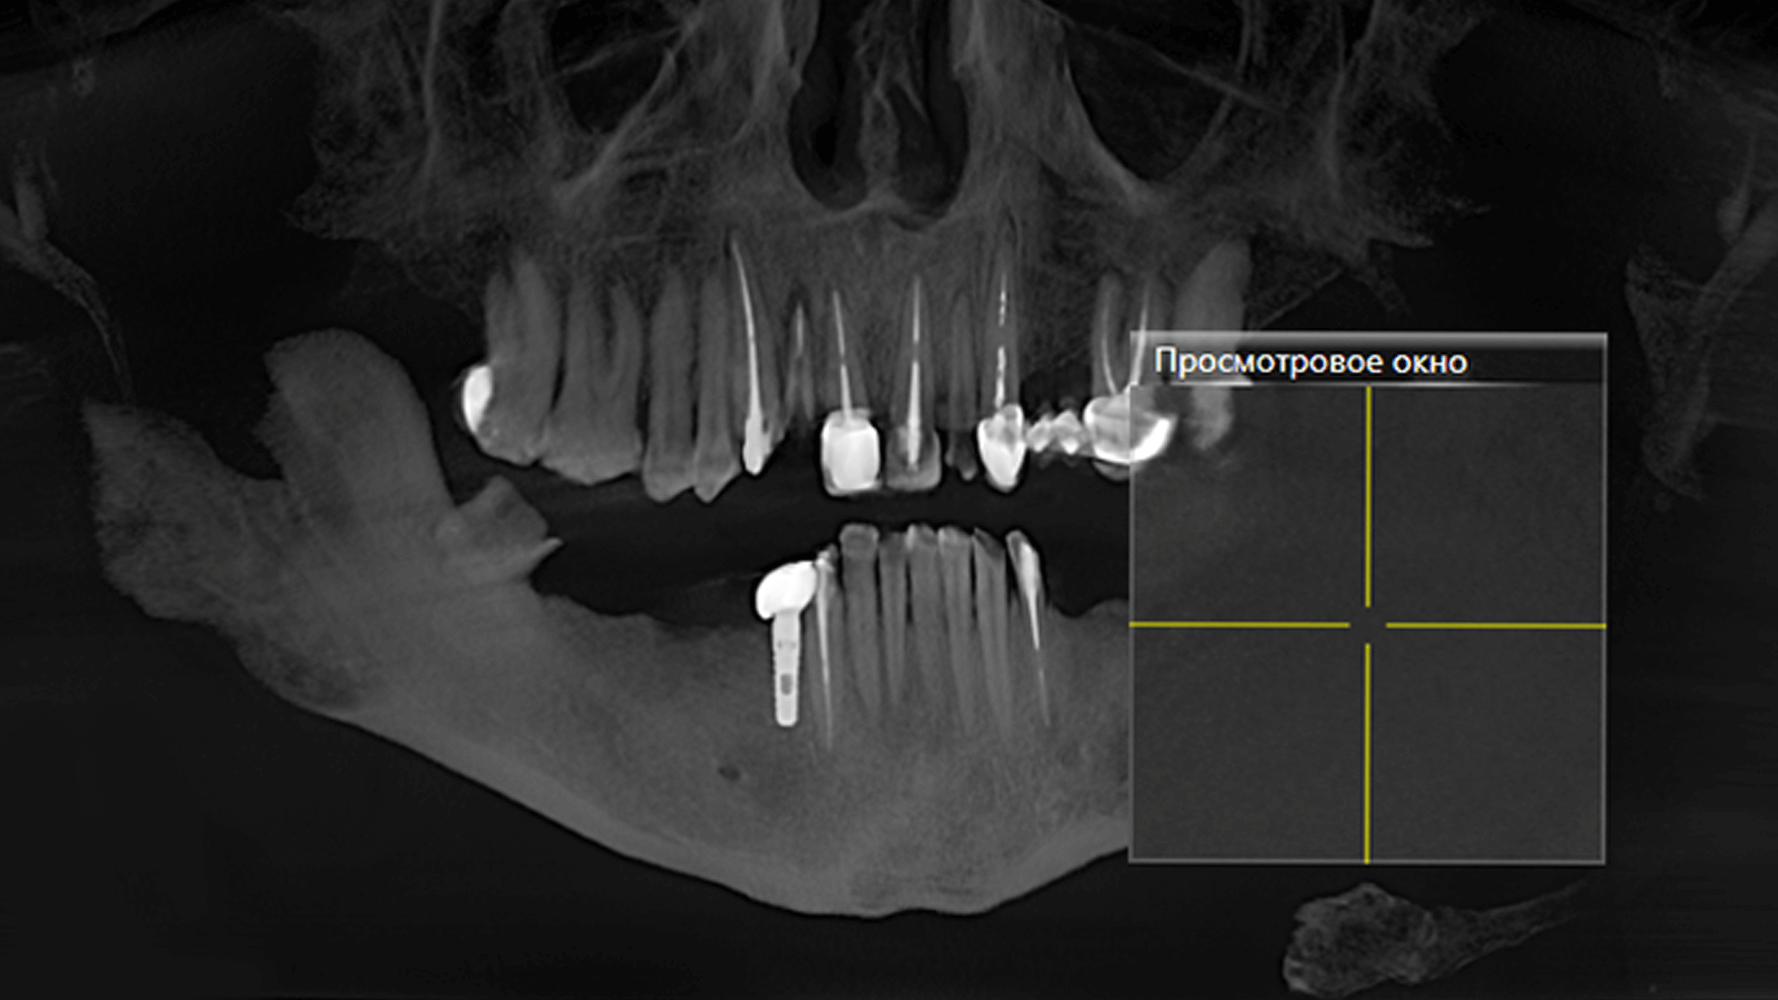

При осмотре пациента было обнаружено отсутствие восьми зубов: 5, 6, 7, 8 с правой и левой сторон на нижней челюсти. Нижние фронтальные зубы были поражены в результате патологического стирания вызванного массивной антагонистической конструкцией (металлокерамические коронки) на фронтальных зубах верхней челюсти. После 3D КТ-диагностики, осмотра и выслушав пожелания пациента, предложили следующий план лечения:

На первичной консультации врач провел осмотр полости рта, оценил КТ-снимки, составил план лечения и согласовал его с пациентом.